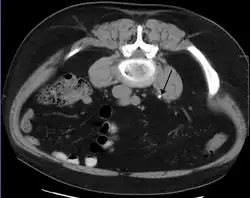

Otherwise a noncontrast helical CT scan with 5 millimeters (0.2 in) sections is the diagnostic method to use to detect kidney stones and confirm the diagnosis of kidney stone disease.[13][47][51][52][7] Near all stones are detectable on CT scans with the exception of those composed of certain drug residues in the urine,[53] such as from indinavir. Calcium-containing stones are relatively radiodense, and they can often be detected by a traditional radiograph of the abdomen that includes the kidneys, ureters, and bladder (KUB film).[53] Some 60% of all renal stones are radiopaque.[51][54] In general, calcium phosphate stones have the greatest density, followed by calcium oxalate and magnesium ammonium phosphate stones. Cystine calculi are only faintly radiodense, while uric acid stones are usually entirely radiolucent.[55]

Bilateral kidney stones can be seen on this KUB radiograph. There are phleboliths in the pelvis, which can be misinterpreted as bladder stones. -